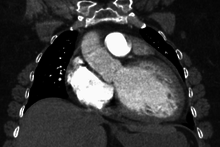

| Mouse heart slice showing dilated cardiomyopathy | |